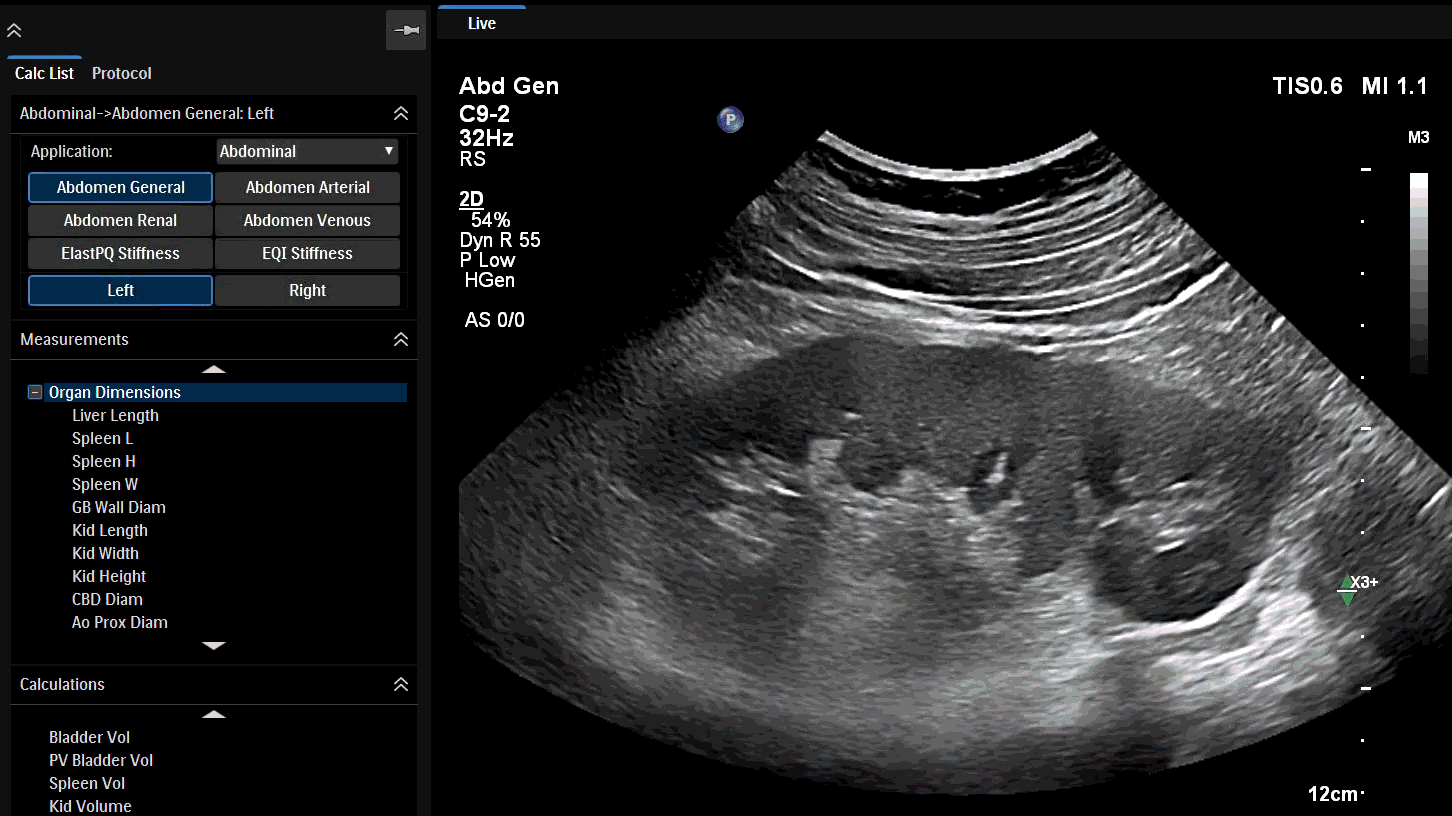

AI-driven Auto Measure Abdomen - Philips